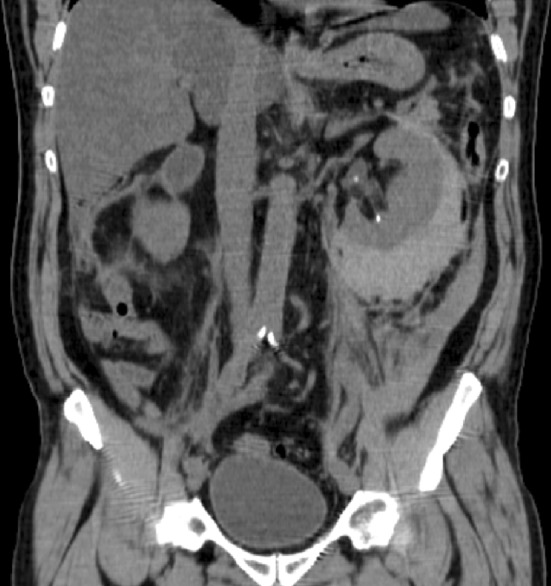

Disintegration of stones should always result in fragments or small stones aimed to be eliminated with urine through the ureter. Accumulation of impacted fragments in the ureter causes obstruction (Fig. 5). This condition is termed “Steinstrasse”, which increases with the initial stone volume. Both isolated stone fragments and “steinstrasse” can in most cases advantageously be treated and eliminated with repeated SWL.

Fig. 5.

This is a typical steinstrasse in the distal left ureter. Columns of fragments are seen after all stone disintegrations, but steinstrasse is the clinically important condition in which the fragment accumulation is associated with obstruction to the urine flow

To avoid the problem of obstruction caused by large fragment volumes, it is helpful to insert an internal stent before stone disintegration [61]. This procedure is in most cases recommended for stones with a diameter exceeding 20 mm or stone surface area above 200–300 mm2 (Fig. 3). Despite reports in the literature that stenting is not necessary, it is the authors’ opinion that many problems can be avoided with such precaution. Insertion of an internal stent can in most patients conveniently be carried out under local anaesthesia, with or without administration of low-dose analgesics and sedatives. Only very exceptionally will ureteroscopy be necessary to remove a “Steinstrasse”. Most cases can be dealt successfully with SWL, with or without insertion of a ureteral stent (Fig. 6). Childrens’ ureters have a much better transport capacity than those of adults and stenting can, therefore, be omitted in most children also before SWL of larger stones [87]. Stenting can also be recommended for weak persons in whom every kind of obstruction might be deleterious.

Fig. 6.

Fragment accumulation alongside an internal stent. This stent was gently passed through the fragment mass before repeated SWL